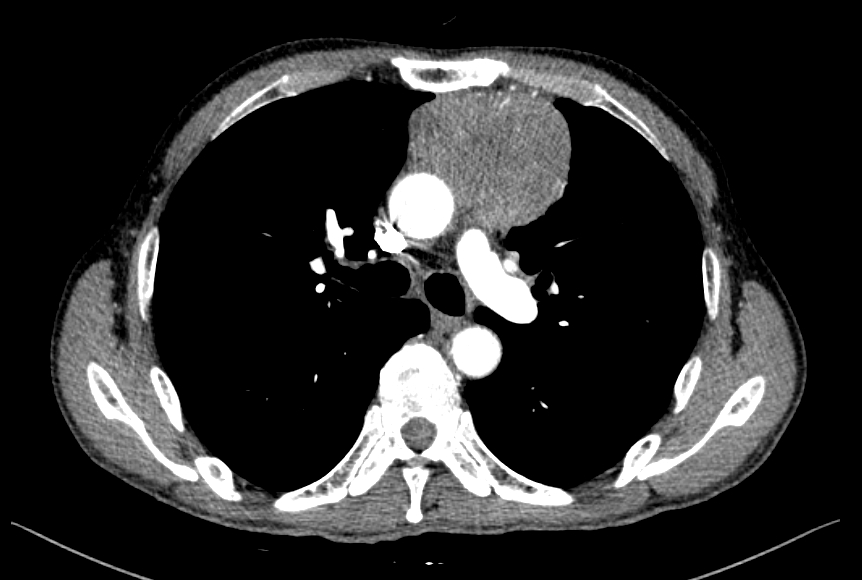

¿©·¯ ¼±»ý´ÔµéÀÌ ÀǰßÁֽŠ¹Ù¿Í °°ÀÌ lateral »çÁø»ó ÀǽɵǾú´ø anterior mass Chest CT »ó¿¡¼­µµ °üÂûµË´Ï´Ù.

Chest CT

A heterogenous enhancing mass at the Lt. anterior mediastinum.

The mass abuts the ascending aorta and MPA, without definite invasion.

Minimal pericardial effusion is visible, r/o pericardial invasion.

Unremarkable on the both lungs.

IMP: Anterior mediastinal mass

DDx) invasive thymoma, thymic carcinoma, Hodgkin's lymphoma (nodular sclerosing)